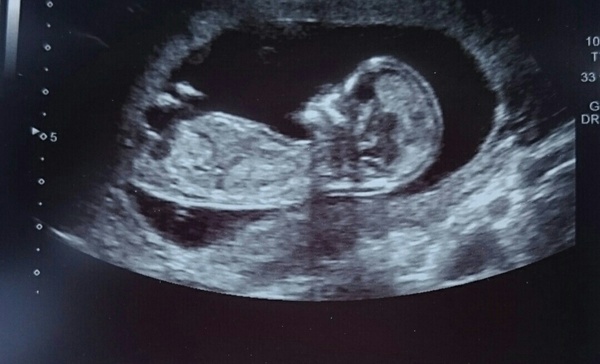

I just wanted to put up a pic of my scan. It was a few weeks ago when I was 13w. Hope you don't mind :)

PS HP07 that baby has a lovely profile!! I think yours is going to be cuter than mine!!

Thank you Tabby :) baby has been very co-operative so far for the scans, although it was fast asleep! I had to roll onto my side to wake it up but it just rolled over and went back to sleep with its back to us instead like a stroppy teenager! Did you find out the sex Tabby? We're keeping our a surprise.